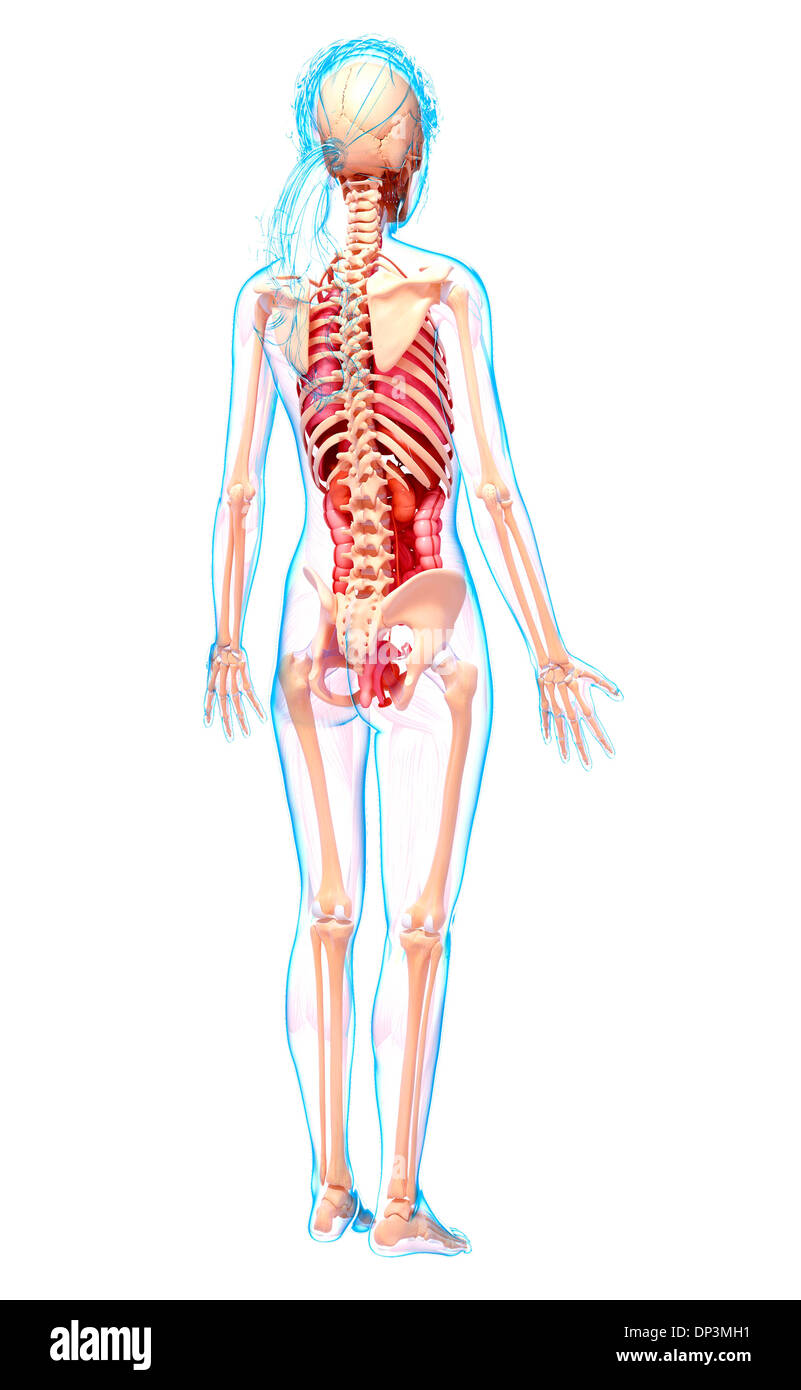

, Artwork Banque D'Imageshttps://www.alamyimages.fr/image-license-details/?v=1https://www.alamyimages.fr/artwork-image65235549.html

, Artwork Banque D'Imageshttps://www.alamyimages.fr/image-license-details/?v=1https://www.alamyimages.fr/artwork-image65235549.htmlRFDP3MH1–, Artwork